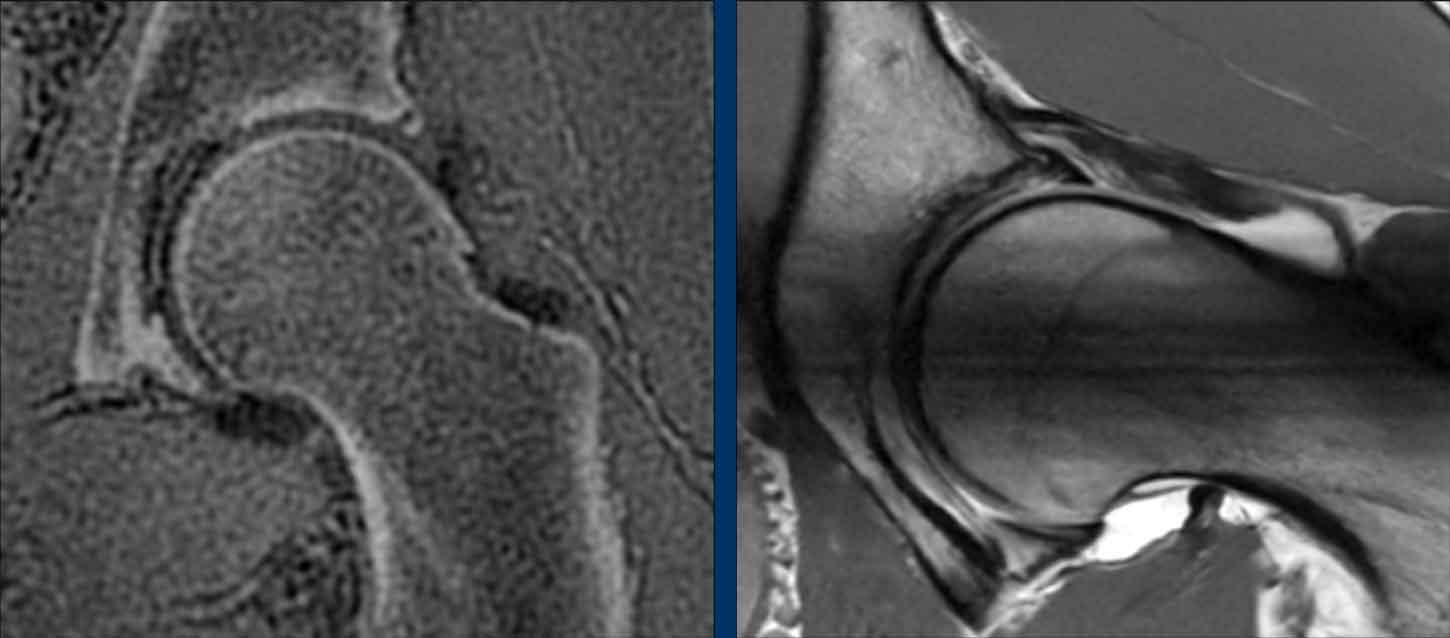

Những hình ảnh này là của một phụ nữ 28 tuổi tham gia tập CrossFit ở cấp độ chuyên nghiệp. Cô ấy đã có các triệu chứng ở vùng hông trái, cụ thể là ở phía trước, trong suốt một năm qua. Các triệu chứng trở nên nặng hơn khi thực hiện động tác squat và gấp hông.

Khi thăm khám, ghi nhận giảm biên độ gấp háng (đau ở 120°) và hạn chế xoay (giới hạn ở 20° và đau).

Đầu tiên hãy nghiên cứu hình ảnh X-quang.

Sau đó tiếp tục với các hình ảnh chi tiết…

Mặc dù các phát hiện còn tinh tế, nhưng có bằng chứng về hình thái Pincer, được chỉ ra bởi dấu hiệu giao thoa và dấu hiệu gai ngồi.

Sự xoay ngược của ổ cối dẫn đến gai ngồi nổi bật hơn và khiến phần trên của thành trước ổ cối chồng lên thành sau trên hình ảnh.

Ngoài ra, có dấu hiệu nhẹ của hình thái Cam.

Continue with the MR-arthrogram…

Sau đó, chụp cộng hưởng từ khớp được thực hiện, cho thấy rách sụn viền ở vùng trước trên.

Ban đầu, bệnh nhân được điều trị bảo tồn bằng vật lý trị liệu, nhưng kết quả không đạt yêu cầu.

Sau đó, một thủ thuật nội soi khớp đã được thực hiện, bao gồm việc tạo hình lại chỗ nối chỏm-cổ xương đùi (mũi tên), mang lại sự cải thiện đáng kể.